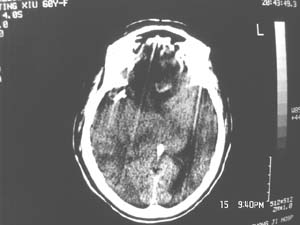

女,60岁,反复头痛3天,呕吐3小时伴昏迷10分钟入院检查。

右额叶占位,有占位效应,中线偏移,病灶位于镰旁,呈囊实性并有钙化,

考虑:1.脑膜瘤。2.胶质瘤。

理由:1.病灶位于前颅凹及镰旁,有明显占位效应---支持脑膜瘤。

2.病灶呈囊实质性并有条状钙化,符合胶质瘤改变;

另外也不排除包虫病的可能。

右额叶占位,有占位效应,中线偏移,病灶位于镰旁,呈囊实性并有钙化 kaolv  少枝胶质瘤。胶质瘤。

结合病史这么短,病情进展迅速,从常见病多发病方面考虑,比较符合脑血管病,故首先考虑出血性脑梗塞;

其次考虑脑肿瘤,是否并有瘤卒中,还是钙化我觉得ct值很重要;

病变范围较大,累及左额叶,内见钙化。及高密度灶。考虑;胶母伴卒中可能大。

边缘见条片钙化支持少支胶质瘤